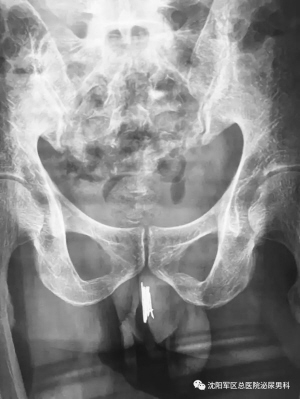

本报讯(华商晨报记者 王丽娜)一年多时间频繁尿血,沈阳35岁的男子求医无果后,到沈阳军区总医院泌尿男科就诊。 经过详细检查后,医生发现,男子的尿道内竟然有多达15根家用缝衣针。这些钢针都是男子自己在一年左右的时间内陆续放进去的。 医生提醒,尿道口异物患者并不少见,油笔芯、温度计、铁丝在临床上都看到过,但是这样做是非常危险的,严重了可能无法排尿,需要手术改道甚至终身残疾。 罕见病例: 男子尿道口内插15根缝衣针 6月20日15时许,沈阳军区总医院泌尿男科副主任医师曹志强开始了一台艰难的手术。 台上的患者是一名35岁的未婚男子,尿道内塞入了15根长短不一的缝衣针,最长的约8~10厘米,最短的也有5~6厘米长。 男子在家属的陪同下,最近因尿道疼痛不适多家医院就诊后,转到沈阳军区总医院院。拍片提示,针均卡在大概膜部尿道位置。 医生了解到,从一年多前开始,男子分多次由尿道外口塞入了钢针,均为针鼻儿一头向内、针尖向外,因此塞入时并没有很疼。 但钢针留在体内无法自行取出,时间长了,尿痛、尿血等问题让他难以忍受,只得多方求医。 如此多的尿道异物,传统的治法肯定是开刀取出,但患者却不希望开刀,因此跑了多家医院也没有治好。 为此,曹志强医生在泌尿男科主任刘龙的指导下,选择了电切镜、输尿管镜、腹腔镜多种器械的手术方案,通过几根导丝将器械从尿道口送入尿道,将钢针一点点“拔”了出来。 医生提醒: 癖好不是病但需注意安全 “手术大概做了一个半小时左右,结束的时候我的手都累得发抖了,满头是汗,确实不容易。”曹志强说,其实这样的患者,在男科并不算罕见。 曹志强表示,男科还曾接诊过尿道内塞油笔芯、温度计、铁丝等异物的患者,男女都有。“有学者称这种有特殊癖好的人为‘性怪癖’的一种,尿道疼痛刺激或摩擦刺激能够使他们获得一种满足感。” 医生表示,这并不能说是一种疾病,但在方法上确实需要注意安全至上。因为钢针、笔芯、温度计等异物一方面不够清洁,另一方面容易折断或者存在易伤人的尖锐端,极易对人体造成损伤。一旦异物卡在体内无法取出,还会造成尿道狭窄、尿漏等问题,最严重的将无法排尿。 钢针卡在尿道外口 |